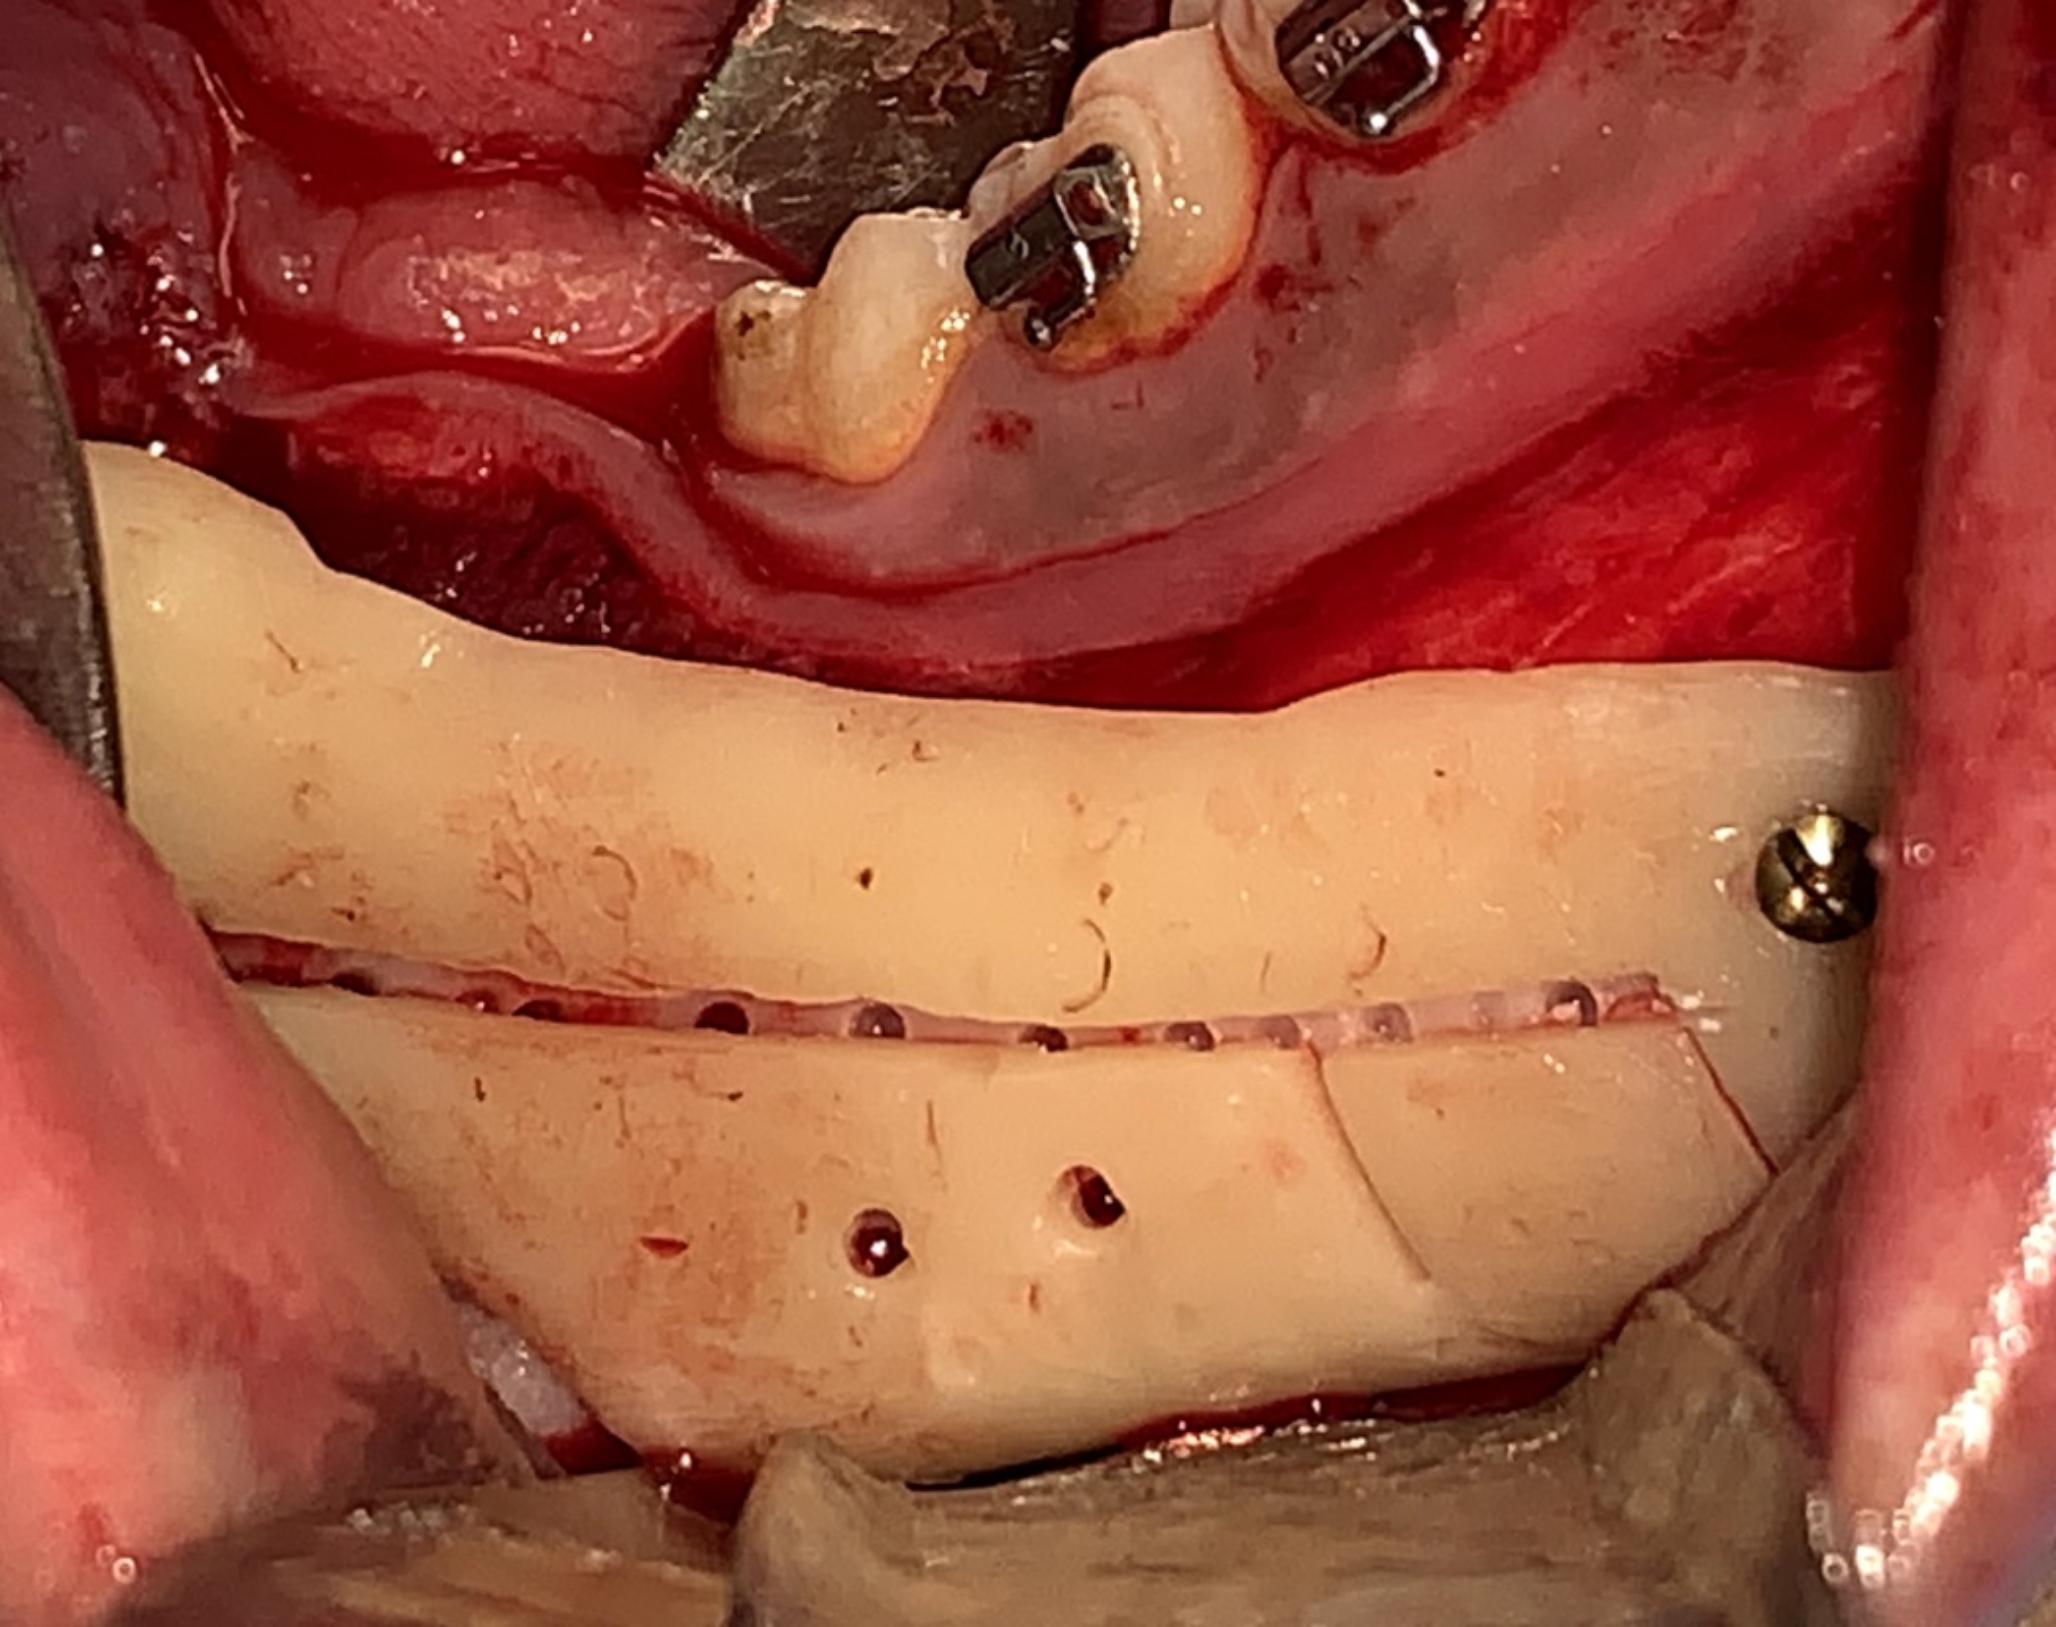

Fig. 4

Intraoperative photograph showing the guide seated in place

Based on the preoperative clinical and radiographic assessment and virtual planning enrolled skeletal class III patients were categorized in to patients requiring mono-maxillary or bimaxillary surgical intervention. The surgical procedure was performed under general anesthesia. In Bi-maxillary cases, the maxillary surgery was performed first, segment was mobilized and positioned using a cutting and drilling surgical guide associated with pre-bent plates osteosynthesis, then the mandibular surgery was performed. The mandibular surgery starts with bilateral intraoral mandibular incisions. The surgical guide was placed in position (Fig. 4). Screw holes and osteotomy lines were performed. A reference marking points were performed using a surgical fissure bur through the nerve tracing central trough of the surgical guide to mark the nerve pathway (Fig. 5). The device was removed, and the marked pathway was followed using a sinus lifting round stone to uncover the lateral cortical bone overlying the nerve. The nerve was then carefully repositioned in a lateral and upward direction using a nerve hook (Fig. 6). The intracanal osteotomy was completed through the uncovered mandibular canal using a reciprocating saw to connect the upward horizontal ramus cut with the two vertical inferior border cuts. The osteotomy lines were confirmed using spatula chisels then the proximal and distal segments were successfully separated. The distal interferences were removed while the IAN was safely lateralized, and the mandibular segments were repositioned guided with the pre-bent plates and screw holes (Fig. 7).